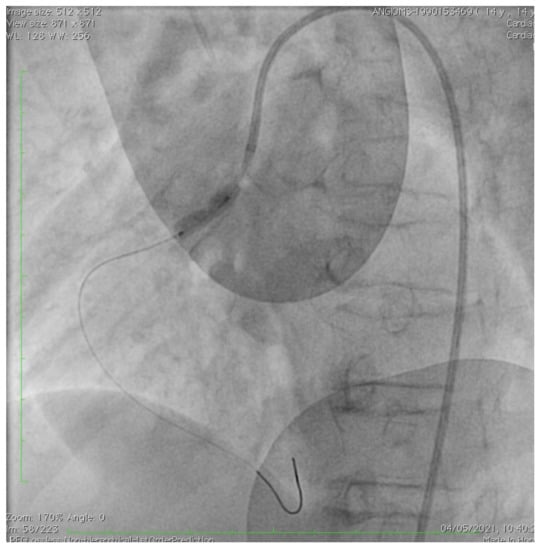

Acute Coronary Syndrome Treated with Percutaneous Coronary Intervention in Hutchinson–Gilford Progeria

2. Case Description

De Simone, L.; Chiellino, S.; Spaziani, G.; Porcedda, G.; Calabri, G.B.; Berti, S.; Favilli, S.; Stefani, L.; Santoro, G. Acute Coronary Syndrome Treated with Percutaneous Coronary Intervention in Hutchinson–Gilford Progeria. Children 2023, 10, 526. https://doi.org/10.3390/children10030526